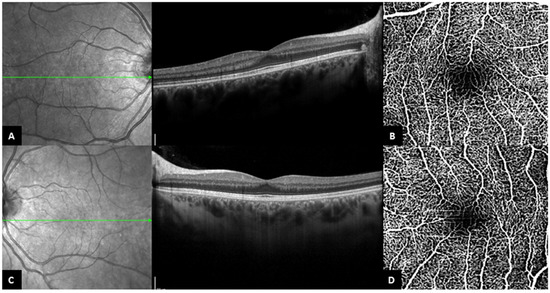

Figure 2. Representative case (Patient 2 right eye). (A). Autofluorescence of the right eye showing the intense hyperautofluorescence of the material under the macula. (B). OCT-A of the right eye with bridging vessels across the foveal avascular zone (the slabs contain the superficial and the deep capillary plexuses together). (C). Corresponding OCT-A B-scan of the right eye showing the decorrelation signal in inner retinal layers. (D). Central OCT B-scan from the same patient, with persistence of the outer plexiform layer.

Sixty-six eyes of thirty-three patients (16 females (48.5%) and 17 males (51.5%)) with Best disease were analyzed. Overall, the mean age of subjects was 31.2 ± 19.0 years old. The diagnosis of Best disease was established based on genetic confirmation for 13 patients (39.4%), an EOG Arden ratio less than 170% for 4 patients (12.1%), clinical presentation and an EOG Arden ratio between 170 and 179% for 1 patient (3.0%), family history and clinical presentation for 10 patients (30.3%), and finally, clinical presentation alone for 5 patients (15.2%) (Table 1). A total of seven eyes of six patients could not be evaluated because of the poor quality of OCT images and were excluded from the study. Therefore, only 59 eyes of 32 patients were analyzed (Figure 1). Based on the foveal appearance on B-scan SD-OCT, 16 eyes (27.1%) of 9 patients had a fovea plana appearance (‘FP group’) (representative case, Figure 2) and 43 eyes (72.9%) of 23 patients did not have fovea plana appearance (‘no FP group’). The mean age of subjects was statistically lower in the ‘FP group’ compared to the ‘no FP group’ [19.2 ± 14.1 and 35.9 ± 18.9, respectively (p = 0.01)]. Otherwise, medical records and demographic criteria were all equal between both groups (Table 2 and Table 3). Using the Thomas classification (14), the grading of foveal hypoplasia was atypical for 14 eyes (87.5%) and grade 1b for 2 eyes (12.5%) (Table 1).

3.3. OCT-A Findings

Out of the 16 eyes with fovea plana appearance on B-scan SD-OCT, 13 eyes had an interpretable OCT-A, which revealed bridging vessels passing through the FAZ in all eyes (representative case, Figure 3) (Table 5). On the other hand, 27 eyes out of the 43 eyes (62.8%) with no fovea plana appearance on B-scan SD-OCT had analyzable OCT-A, with a FAZ identified and measured in all eyes (Table 5). The mean FAZ area was 0.34 ± 0.17 mm2, which was independent of the disease stage (Table 6).